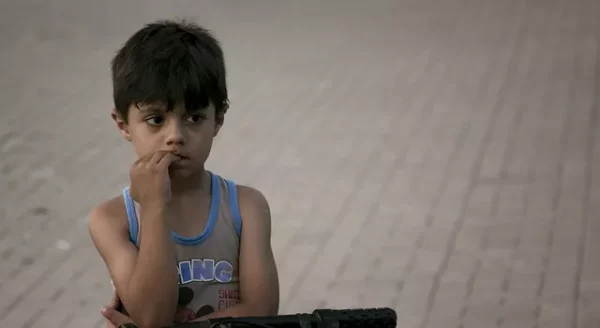

التوأم الطفيلي : جنين في رحم جنين !

في حالة غير عادية احتاجت طفلة مولودة بعملية القيصرية إلى الحصول على عملية قيصرية بعد 24 ساعة من ولادتها لإزالة توأم امتصته في الرحم وتعرف هذه الحالة بالجنين في جنين أو الجنين الطفيلي. حالة جنين في رحم جنين ، تحدث هذه الحالة عادة مع التوائم ، وهي ما يحدث عندما لا تنقسم الأجنة التوائم بشكل […]